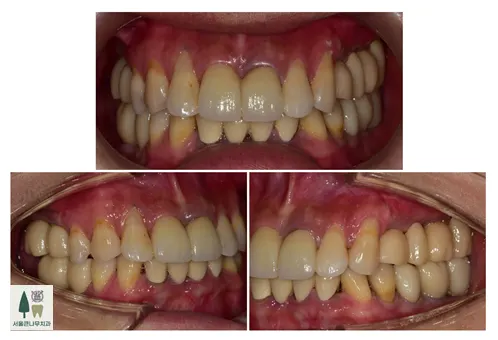

치료 전후 비교사진입니다

치료 후